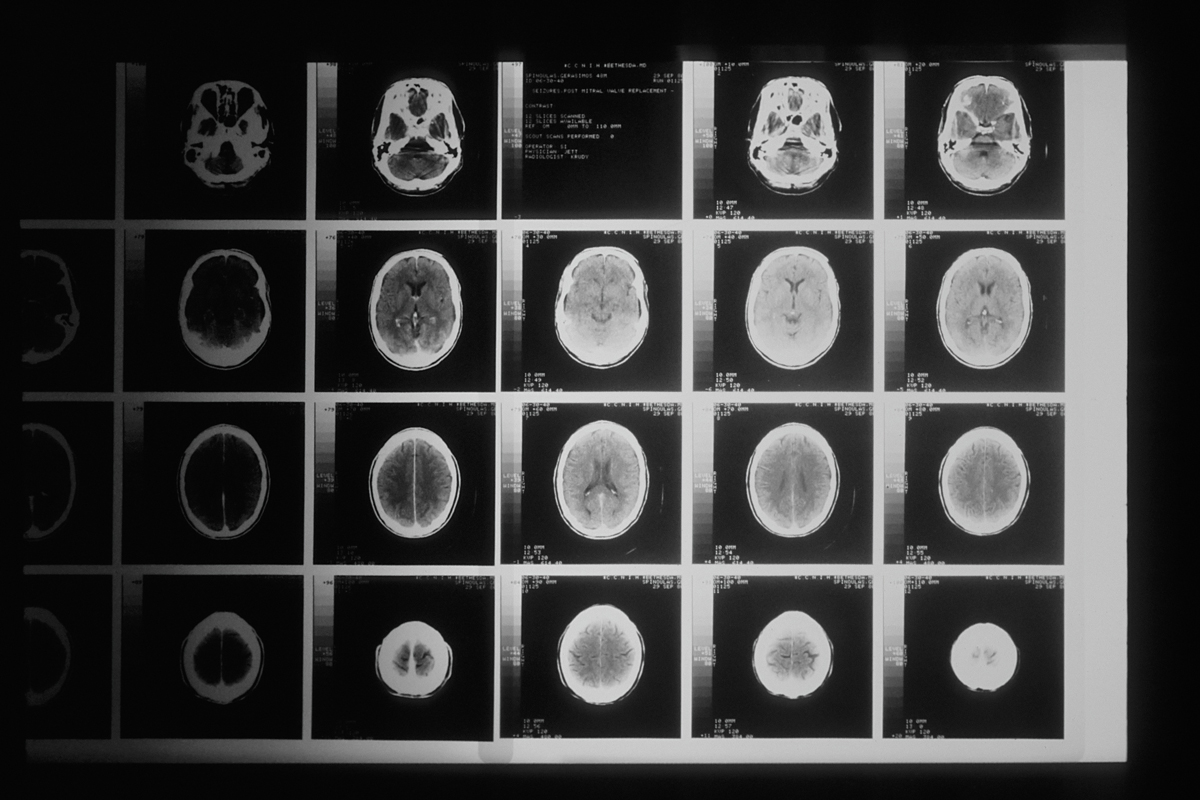

Изображение носит иллюстративный характер. Фото: National Cancer Institute / Unsplash.com